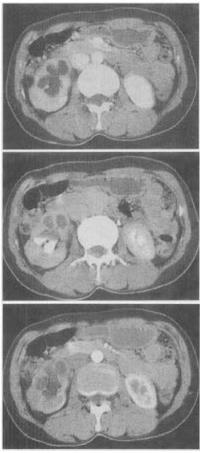

患者,男,33岁,尿频,尿急伴发热月余。尿常规检查:镜下血尿,脓尿。CT检查见图。该患者最有可能患何种疾病()。

A、肾癌

B、肾盂癌

C、肾结核

D、肾囊肿

E、错构瘤

C